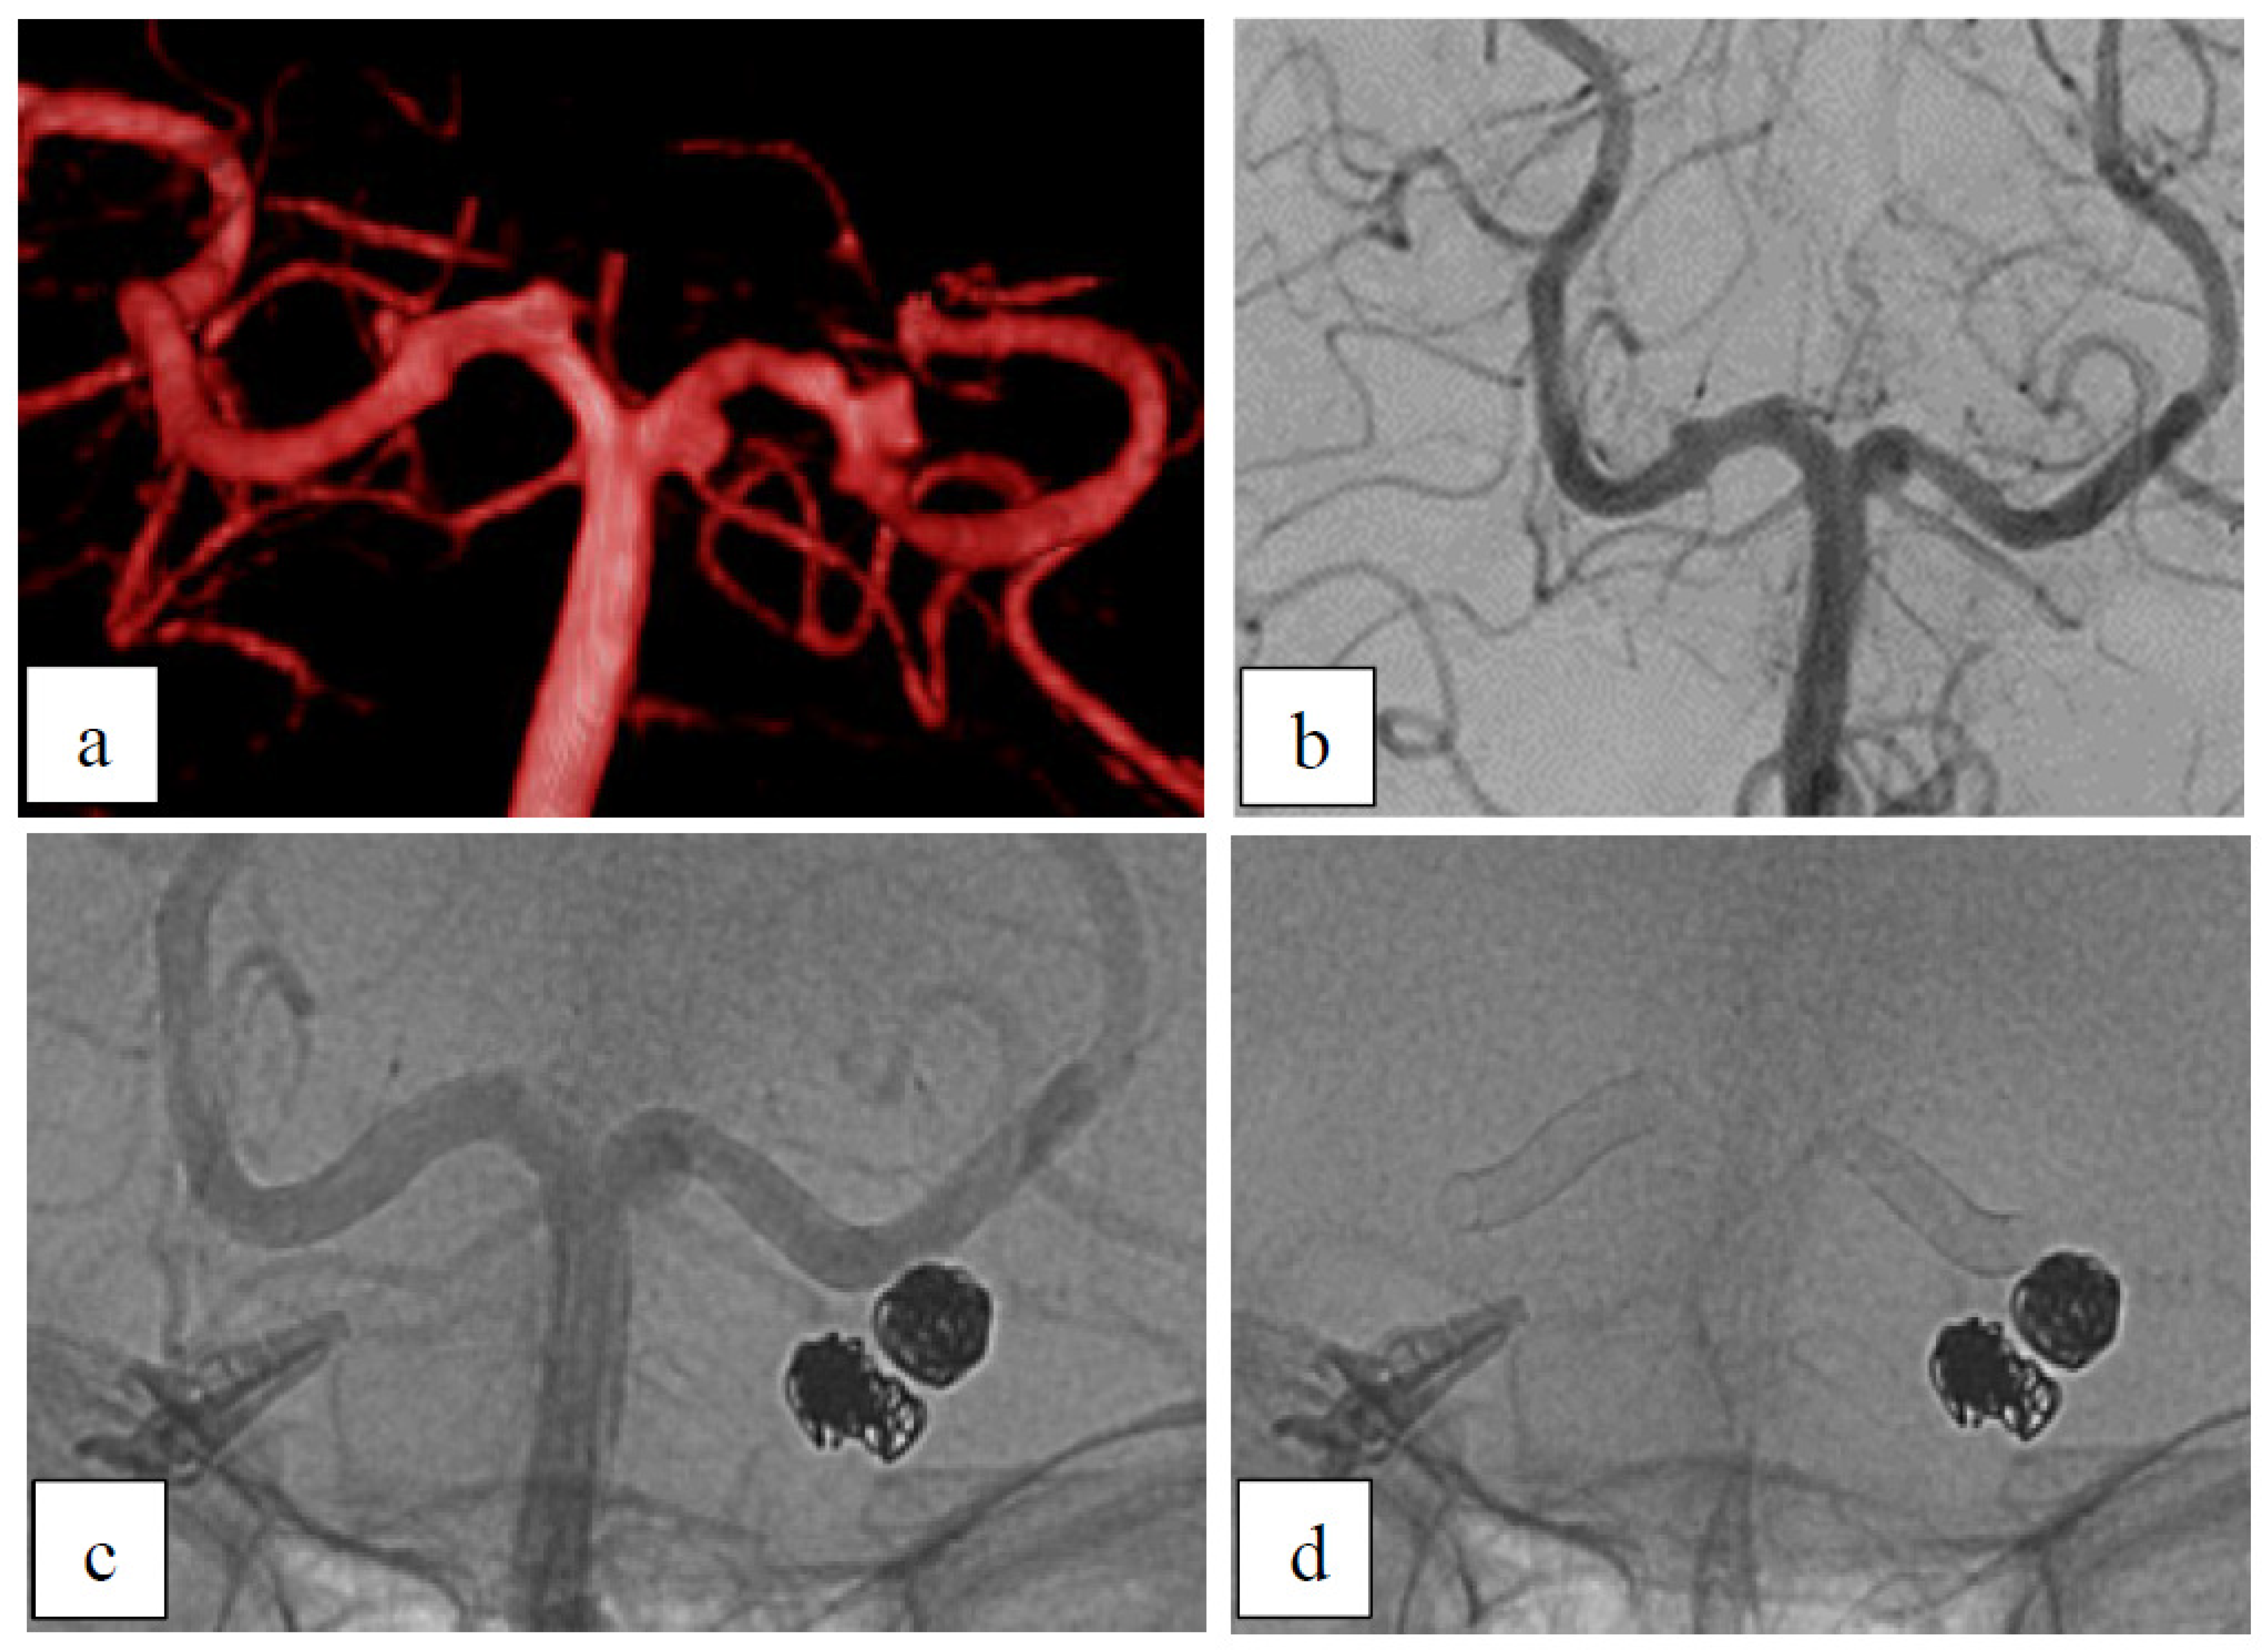

Case 1: Dysplastic Aneurysms

Case 2: Dysplastic Aneurysm with Incorporated Branch

| 50 | f | P1/2 (two aneurysms) | bilateral | dysplastic | no | no | ASA+ Clopidogrel | left: B2 right: B2 | left: 3 | left: D1 right: − |

| 55 | f | A2 (two aneurysms) | right | dysplastic | no | no | ASA+ Prasugrel | prox: B2 dist: A2 | prox: 6 dist: 6 | prox: D1 dist: B2 |

| 1 | 50 | f | P1/2 (two aneurysms) | bilateral | dysplastic | no | no | ASA+ Clopidogrel | left: B2 right: B2 | left: 3 | left: D1 right: − |

| 2 | 55 | f | A2 (two aneurysms) | right | dysplastic | no | no | ASA+ Prasugrel | prox: B2 dist: A2 | prox: 6 dist: 6 | prox: D1 dist: B2 |